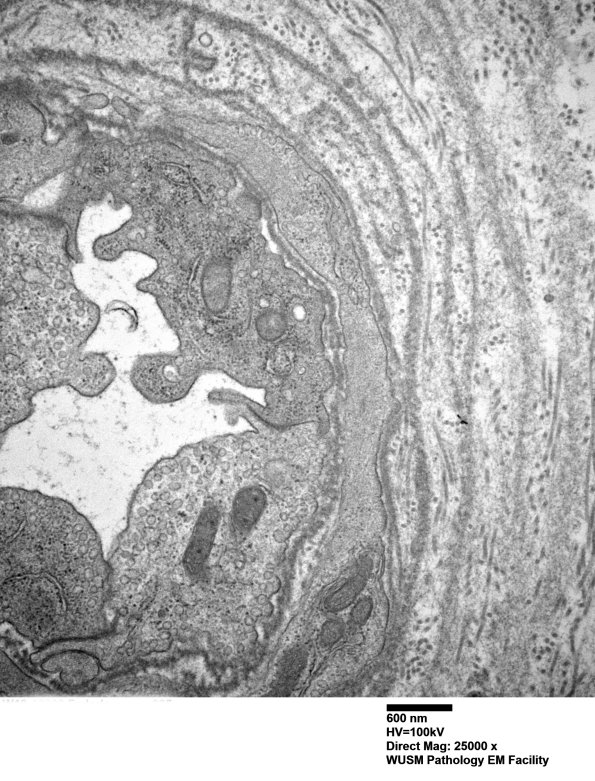

Washington University Experience | VASCULAR | Hypoxia-Ischemia, fetal-neonatal | White Matter | 13C3 (Case 13) EM025 - Copy

13C3 (Case 13) EM025 - Copy